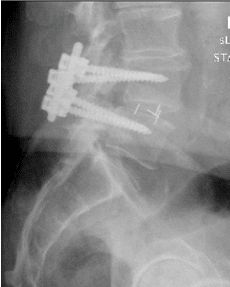

Patient underwent decompression laminectomy with decompression of nerve roots and transforaminal interbody fusion using PEEK (polyether ether ketone) cage and pedicle screw and rod fixation for fusion at L4-5 level.

Fusion was achieved in about 3 months and patient was asymptomatic.